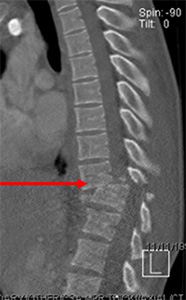

Clinical Example 2

Gentleman after a motor vehicle accident comes into the hospital unable to move his legs. A CT shows a fracture dislocation (arrow). Emergent surgery is done to help realign the fracture as best as possible.